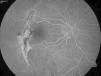

Paciente varón de 28 años que presenta rotura coroidea y hemorragia macular postraumáticas de 24 horas de evolución acude al servicio de urgencias. Se realizó desplazamiento neumático de la hemorragia mediante inyección intravítrea de C3F8 y activador tisular del plasminógeno (rTPA), consiguiéndose la reabsorción de la hemorragia y mejora de la agudeza visual (AV). Al cabo de 3 meses, el paciente acude por empeoramiento de la visión con metamorfopsia, diagnosticándose de neovascularización (NVC) yuxtafoveal en la zona de la rotura, que se trata con una inyección de bevacizumab intravítreo. Un año después, la NVC permanece inactiva y la AV se mantiene en 0,5.

A 28 year-old male attended our Emergency Department with a traumatic choroidal rupture and macular haemorrhage. After pneumatic displacement of the haemorrhage with C3F8 and tissue plasminogen activator, the haemorrhage was reabsorbed and visual acuity (VA) improved. Three months later the patient presented with decreased VA and a juxtafoveal choroidal neovascularisation (CNV) that was treated with intravitreal bevacizumab. One year after a single bevacizumab injection the CNV remained inactive, with a final VA of 0.5.